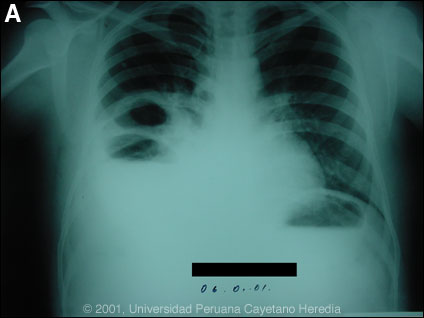

Epidemiology: Grew up on farm in Lake Titicaca region, and has lived in Lima the past 5 years. Non-smoker, no history of or exposure to TB. No EtOH abuse. Physical Examination: Temp 38 degrees C, decreased air entry and rales R base. No hepatosplenomegaly. Labs/X-ray: Hct 40, WBC 10,500 with normal differential. Normal alkaline phosphatase, bilirubin, and transaminases are at upper limit of normal. Urine normal with normal renal function. Chest x-ray is shown [Image A].

Diagnosis: Echinococcus granulosus. Complicated multivesicular echinococcal cyst of the lung with erosion through the diaphragm into the abdominal cavity. No intrahepatic cysts found at surgery.